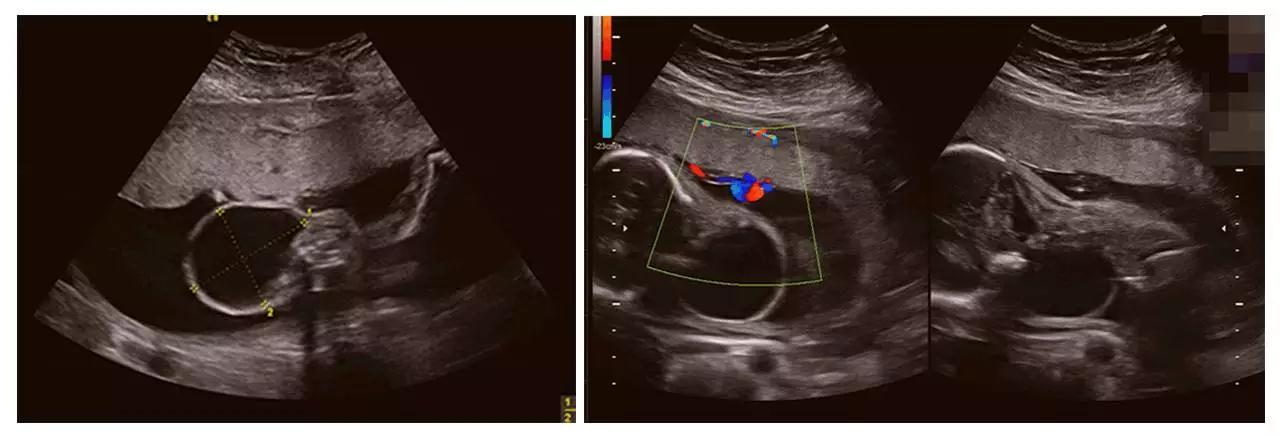

济南艾玛妇产医院引进的GE高清四维彩超(四维彩超)设备,是目前世界上先进的彩色超声设备,远比普通超声设备清晰、准确,被誉为"神奇彩超",是产前筛查的尖端设备,能够多方位、多角度地观察宫内胎儿的生长发育情况,为早期诊断胎儿先天性体表畸形和发育异常提供科学依据,以便尽早的进行治疗。有效防止和减少新生儿出生缺陷的发生。

美GE不仅能提供包括腹部、血管、小器官、产科、妇科、泌尿科、新生儿和儿科等多领域的多方面的应用,而且能够显示未出生的宝宝的实时动态活动图像,为胎儿进行宫内拍“写真”和动态录像,让宝宝拥有完整的0岁相册。通过四维彩超(四维彩超),可以看到宫内胎儿打哈欠、伸懒腰、吮手指等萌萌的动作,让准爸妈们增添了安心和乐趣,不再仅仅是感觉宝宝的呼吸和运动,可以亲眼目睹宝宝的举动和乖巧容颜。还可以打印宫内高清写真,作为送给未来宝宝的珍贵礼物!

成功筛查胎儿畸形的案例(部分)

(右手多指畸形)

(单侧唇裂)

(双侧唇裂)

(左心发育不良)

(胸腹腔积液、全身水肿)

(颈后水囊瘤)

(胎儿左手未见,考虑截肢畸形)

(胎儿颅内结构异常、眼距窄、鼻结构异常...)